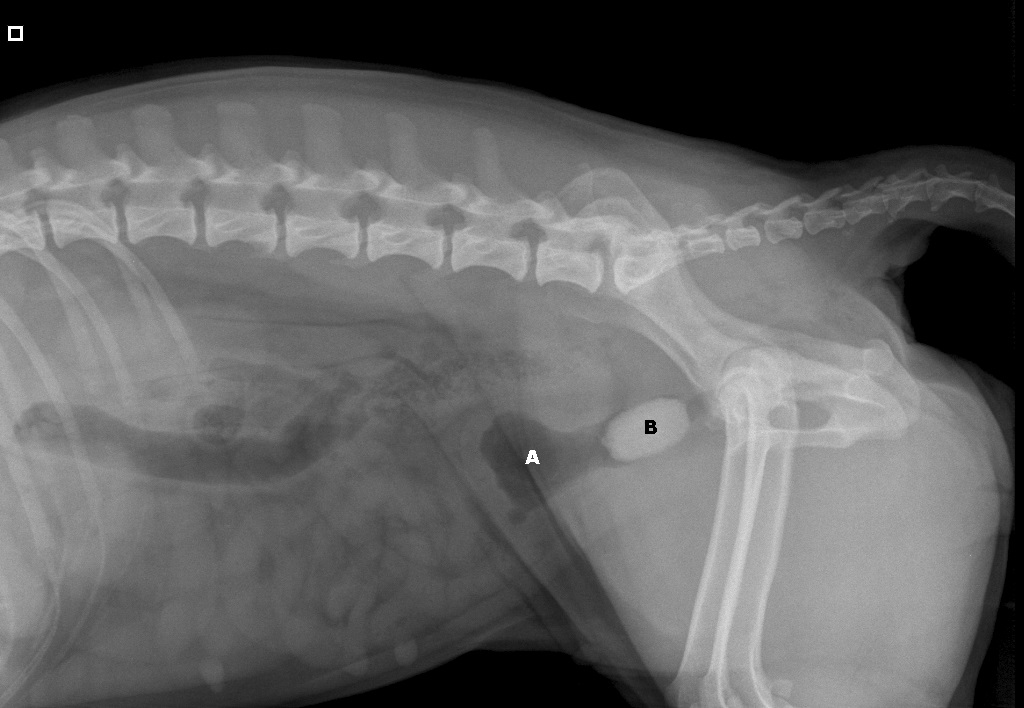

Röntgenfoto van Yvi:

A: blaas

B: de steen